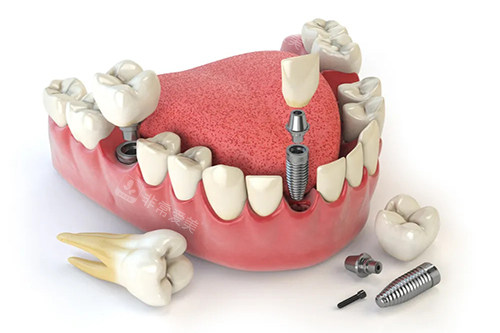

牙齿种植牙模型卡通示意图